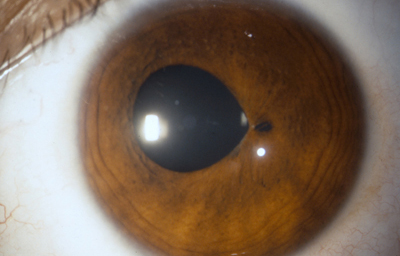

Desplazamientos y anormalidades en la forma de la pupila ( discória, corectópia y policória)

Discória: Referente de las anomalías pupilares

Archivo Fotográfico Dr. Carmen Barraquer. 1989

Corectópia: la pupila en su totalidad, esta desplazada en cualquier dirección. En muchos casos el Iris es normal excepto por su dislocación respecto al centro de la córnea. En algunos casos, se logran ver finas bandas fibrosas que determinan el desplazamiento y se cree pueden ser fibras aberrantes zonulares ( vítreo terciario); otros, consideran que pueden venir de una etapa cuando el vítreo primario ya ha desaparecido, y el vítreo secundario ( condensado formando el Haz Istmico de Druault) todavía esta unido a mesodermo del Iris.

Es muy posible que la persistencia de cualquiera de esas bandas vítreas tempranas en continuidad con el mesodermo iridiano pueda producir una deformación pupilar; su naturaleza avascular y ectodérmica explicaría su aspecto clínico.

Policória: significa la presencia de varias pupilas en un Iris, es un hallazgo extremadamente raro, aclarando que el término se debe emplear solamente, para los casos en que la apertura esta rodeada por un esfínter completo; si no, es una policoria falsa.

Policoria falsa en midriasis OI: sinequia en el borde pupilar temporal con banda fibrosa 3 a 4; se ve el collarete y el esfínter periféricos a la pequeña pupila, lineas de tracción superiores e inferiores hacia el puente que separa las 2 aperturas de la 1 a las 5 - dentro de apertura pequeña, parece existir un remanente de membrana pupilar.

Archivo Fotográfico Dr. Carmen Barraquer. 1983